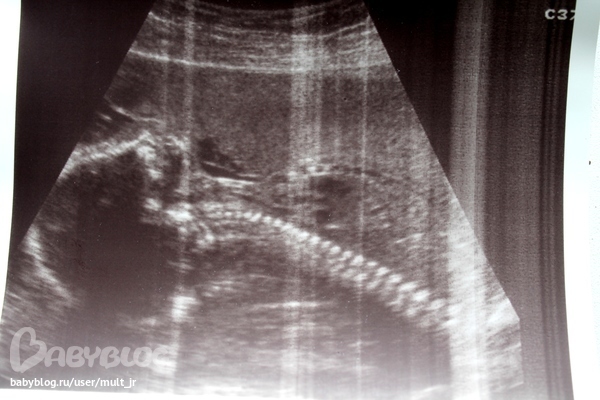

2й скрининг, узи))

А вот и моя кисонька!